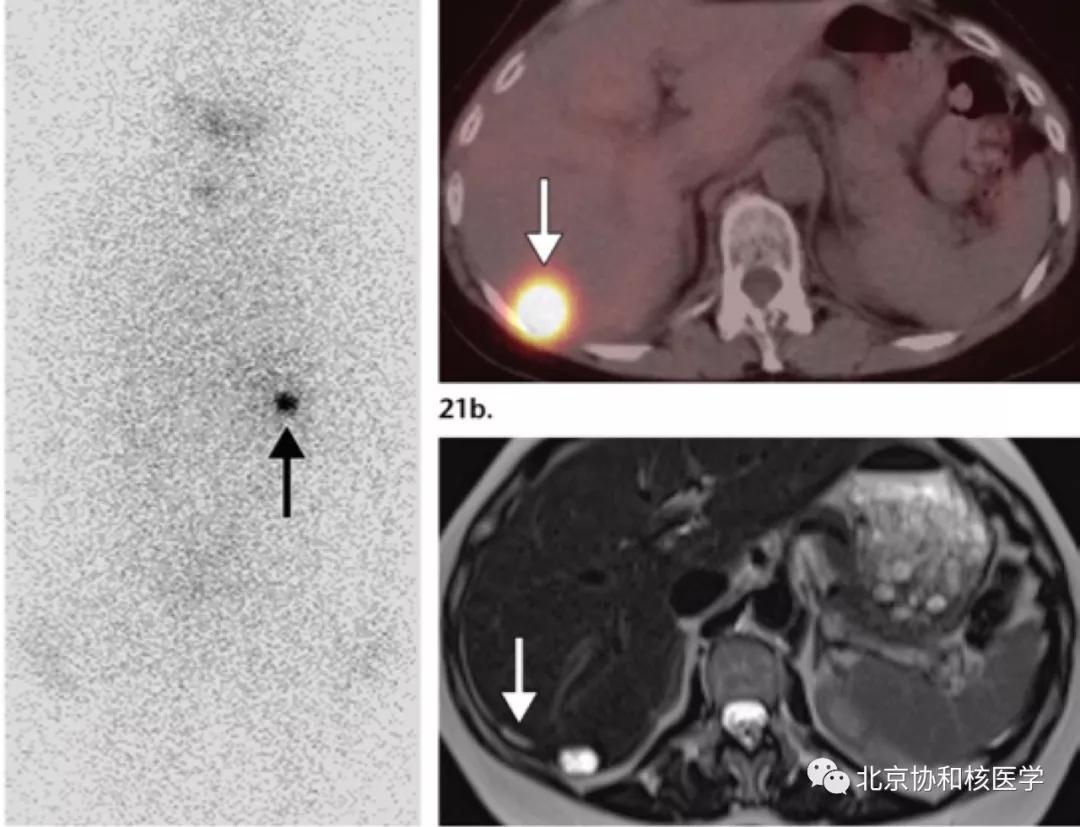

鼻骨骨样骨瘤所致碘摄取,腹部另可见由于巨大肾囊肿所致碘异常摄取: